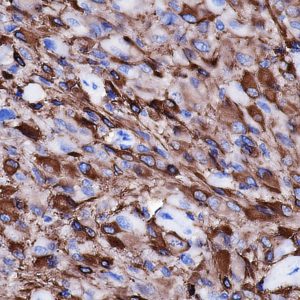

Anti-YAP

YAP encodes a nuclear effector of the Hippo signaling pathway which plays a pivotal role in regulating tissue growth and organ size. Deregulation of the Hippo pathway causes tumor formation and malignancy and hence, YAP may function as a potential target for cancer treatment. YAP is expressed at high levels in the lung, placenta, prostate, testis and ovary.

| Tissue Type/Cancer Type | Breast Carcinoma Tissue |